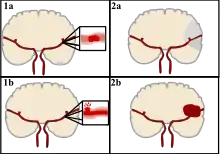

Strokes can be classified into two major categories: ischemic and hemorrhagic.[18] Ischemic strokes are caused by interruption of the blood supply to the brain, while hemorrhagic strokes result from the rupture of a blood vessel or an abnormal vascular structure. About 87% of strokes are ischemic, the rest being hemorrhagic. Bleeding can develop inside areas of ischemia, a condition known as "hemorrhagic transformation." It is unknown how many hemorrhagic strokes actually start as ischemic strokes.[2]

Ischemic

In an ischemic stroke, blood supply to part of the brain is decreased, leading to dysfunction of the brain tissue in that area. There are four reasons why this might happen:

Hemorrhagic

There are two main types of hemorrhagic stroke:[28][29]

- Intracerebral hemorrhage, which is basically bleeding within the brain itself (when an artery in the brain bursts, flooding the surrounding tissue with blood), due to either intraparenchymal hemorrhage (bleeding within the brain tissue) or intraventricular hemorrhage (bleeding within the brain's ventricular system).

- Subarachnoid hemorrhage, which is basically bleeding that occurs outside of the brain tissue but still within the skull, and precisely between the arachnoid mater and pia mater (the delicate innermost layer of the three layers of the meninges that surround the brain).